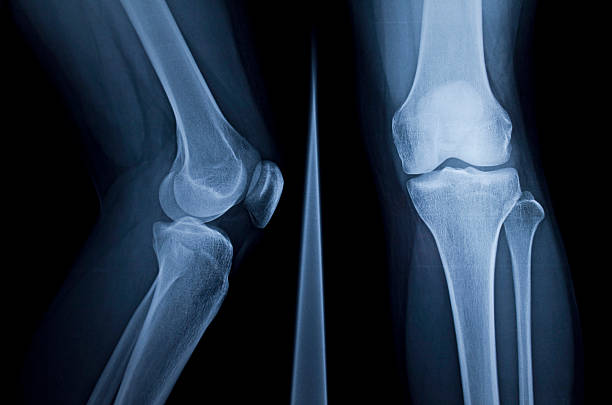

무릎 연골을 정밀 검사하여 찢어진 상태가 좋다는 판단이 선다면 무릎 주변 근력 운동으로 수술을 연기하고 강화하는 것으로 버티는 것이 가능하지만, 파열 전의 상태로 돌아가 반월판 파열된 상태로 살아가야 합니다.

찢어진 연골을 부분적으로 수리하여 원래의 모양으로 회복시키는 치료법도 있는데 얇은 내시경을 삽입하고 미세한 기구로 찢어진 부위를 절제하면서 슬관절의 상태를 관찰하는데 수술 후에는 이틀 정도 재활치료 후 일주일 정도 회복기간을 지나면 일상생활은 가능합니다.